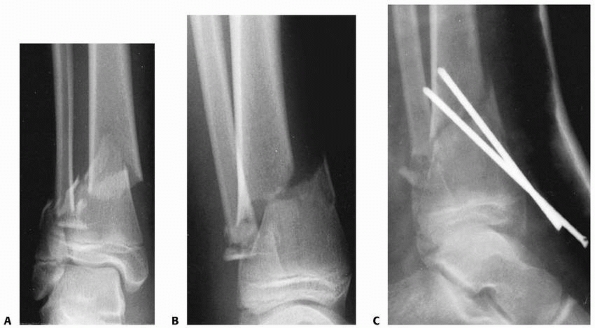

FIGURE 25-29 A,B. Unstable distal metadiaphyseal fractures of the tibia and fibula in a 15-year-old girl. C. This fracture was stabilized with percutaneous pins because of marked swelling and fracture instability.

|